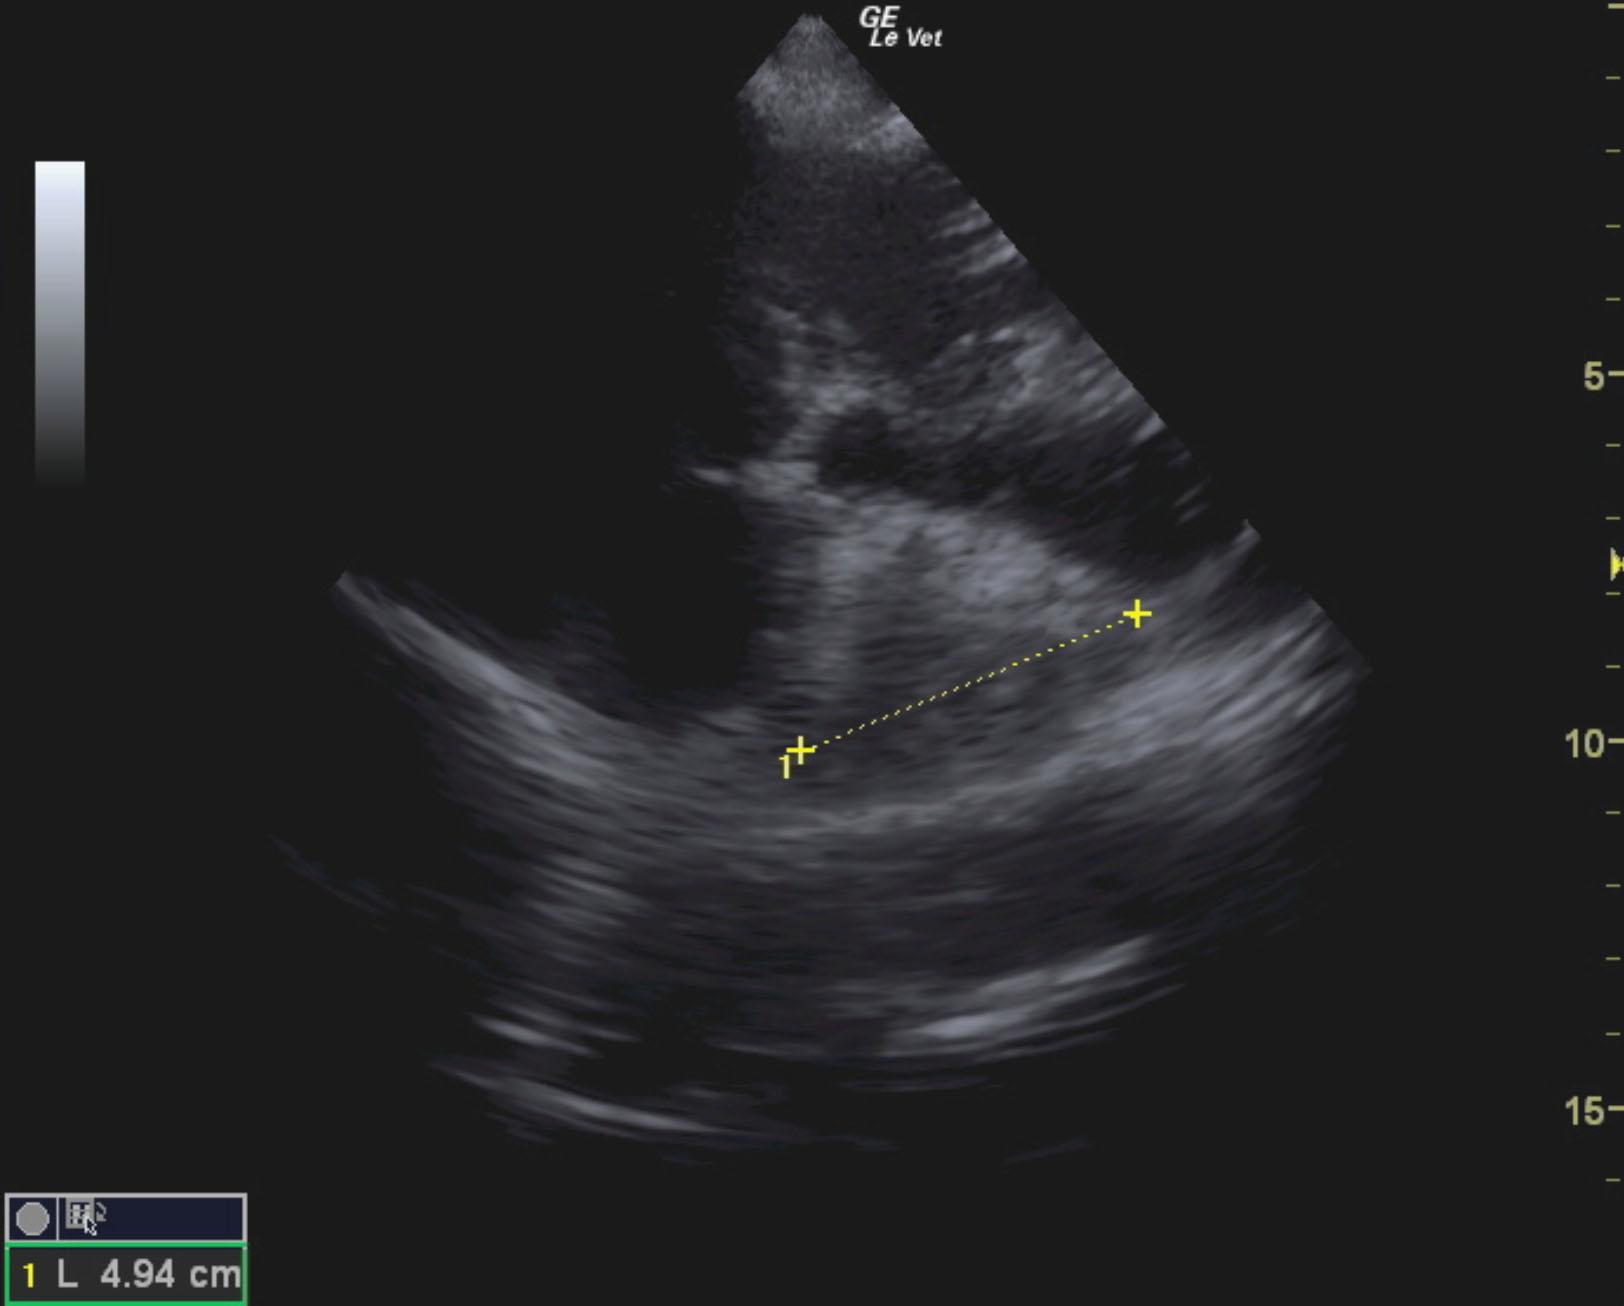

The patient is a canine Mastiff, male, 1 year old who was presented for surgery for the eye, however physical exam revealed muffled heart sounds. Radiographs revealed mass at the heart base.